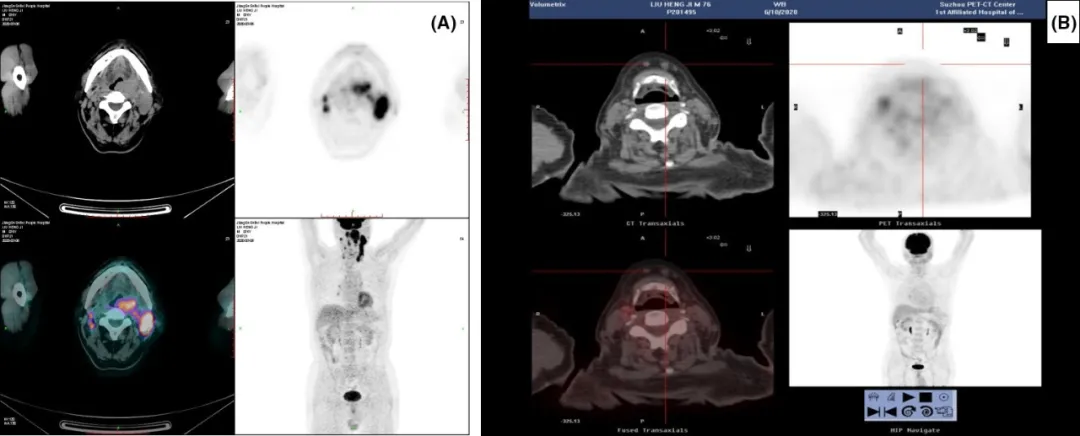

患者为一名76岁男性,咽部梗阻2个月。正电子发射断层扫描显示多个颈部淋巴结病变(图 A)。实验室检查无异常,包括正常的血清乳酸脱氢酶(LDH)水平。

图1 正电子发射断层扫描(PET)/计算机断层扫描(CT)扫描显示诊断时头颈部区域有多个病变(A),患者在四个周期的R2-CHOP(B)后达到完全缓解(CR)

患者接受了6个周期的R2-CHOP(每个周期 第1–5天R-CHOP,第1-14天每天25mg来那度胺口服)。患者在4个周期后评估达到完全缓解,完成第六周期治疗后进入观察随访。截止发稿时,已持续缓解达18个月。